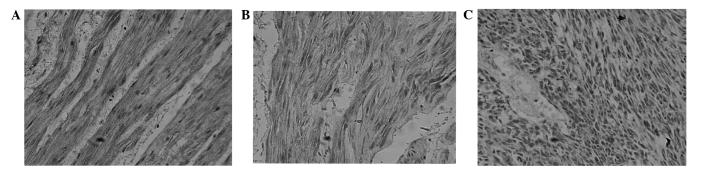

The aim of this study was to explore the expression of tissue factor pathway inhibitor-2 (TFPI-2) in gastric stromal tissue and its clinical significance. TFPI-2 expression was detected by immunohistochemical analysis, RT-PCR and western blotting in tumor, peritumoral and gastric normal tissues from 72 patients with gastric stromal tumors. The level of TFPI-2 expression was observed to be significantly higher in gastric normal tissue than in peritumoral tissue, and was significantly higher in peritumoral tissue than in tumor tissue (P<0.01). As the NIH grade increased, the level of TFPI-2 expression decreased (P<0.01). A low expression level of TFPI-2 was closely associated with invasion and metastasis of gastric stromal tumors. In conclusion, the level of TFPI-2 expression was higher in gastric normal tissue than in gastric stromal tumors. Low expression levels of TFPI-2 may be associated with invasion and metastasis of gastric stromal tumors.

本研究旨在探讨组织因子途径抑制物-2(TFPI-2)在胃间质组织中的表达及其临床意义。采用免疫组织化学分析、逆转录-聚合酶链反应(RT-PCR)和蛋白质印迹法检测72例胃间质瘤患者肿瘤组织、瘤周组织及胃正常组织中TFPI-2的表达。结果显示,胃正常组织中TFPI-2表达水平显著高于瘤周组织,瘤周组织中TFPI-2表达水平显著高于肿瘤组织(P<0.01)。随着美国国立卫生研究院(NIH)分级增加,TFPI-2表达水平降低(P<0.01)。TFPI-2低表达水平与胃间质瘤的侵袭和转移密切相关。总之,胃正常组织中TFPI-2表达水平高于胃间质瘤。TFPI-2低表达水平可能与胃间质瘤的侵袭和转移有关。